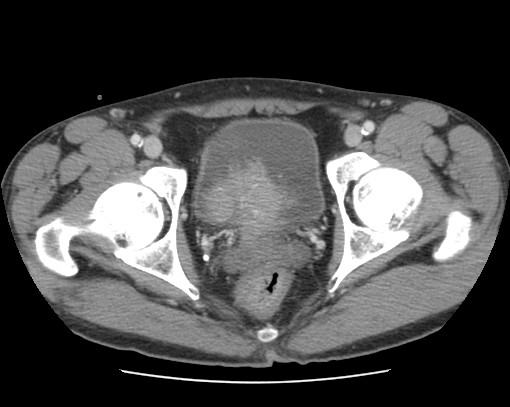

Se realiza nueva TC bifásico abdominopélvio y Uro TC.

CONCLUSIÓN:

- Paciente con numerosas recidivas por Cá vejiga.

- Ha desarrollado un tumor metacrónico en pelvis renal derecha, también responsable de la hidroureteronefrosis.

- Mala evolución radiológica del proceso a expensas de metástasis pulmonares y hepáticas.